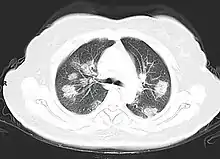

Imaging

Chest CT scans may be helpful to diagnose COVID‑19 in individuals with a high clinical suspicion of infection but are not recommended for routine screening.[159][171] Bilateral multilobar ground-glass opacities with a peripheral, asymmetric, and posterior distribution are common in early infection.[159][172] Subpleural dominance, crazy paving (lobular septal thickening with variable alveolar filling), and consolidation may appear as the disease progresses.[159][173] Characteristic imaging features on chest radiographs and computed tomography (CT) of people who are symptomatic include asymmetric peripheral ground-glass opacities without pleural effusions.[174]

Many groups have created COVID‑19 datasets that include imagery such as the Italian Radiological Society which has compiled an international online database of imaging findings for confirmed cases.[175] Due to overlap with other infections such as adenovirus, imaging without confirmation by rRT-PCR is of limited specificity in identifying COVID‑19.[174] A large study in China compared chest CT results to PCR and demonstrated that though imaging is less specific for the infection, it is faster and more sensitive.[158]